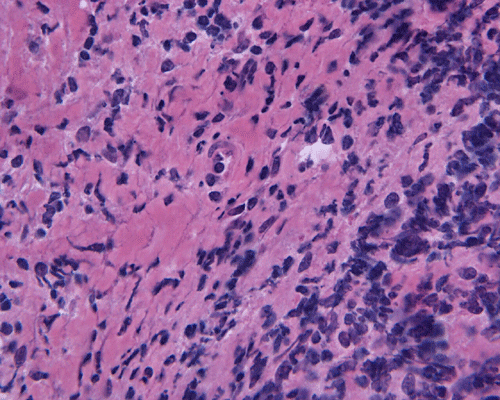

Paraffin sections: The entire volume of the tissue is made up of a granulomatous inflammation with poorly formed granuloma (Panel F, G, and H). The density of the lymphocytes is variable in different areas. In some areas, there is a rather intense lymphocytic infiltration accompanied by scant atypical cells with enlarged nulcei and prominent nucleoli (arrows in Panel I and J, Panel J is a higher magnification of Panel I). These atypical cells are quite easy to be missed. No microorganisms were identified by acid fast stain, PAS stain or GMS stain. The lymphocytes but not the atypical cells are positive for CD20 (Panel K) or CD3 (Panel L). The granulomatous background is strongly positive for CD68 (Panel M). Only rather faint positive staining for placental alkaline phosphatase (PLAP) is demonstrated and the interpretation is difficult as they are present in areas with crush artifact (Panel N). Many of the large, atypical cells are positive for CD117 (c-kit) (Panel O).

Intracranial germinoma is histologically identical to ovarian dysgerminoma and testicular seminoma. There is a tendency to infiltrate adjacent structures and to spread throughout the ependyma, the ventricular system and subarachnoid spaces. Microscopically, they consist of nests, lobules, cords, and/or sheets of large round tumor cells with well-defined borders, clear to pale cytoplasm with artifactual vacuolization, round and centrally located nuclei with open chromatin and prominent round or bar-shaped nucleoli. The cytoplasm is glycogen-rich, making these cells periodic acid-Schiff (PAS)–positive and diastase sensitive. These tumor cells are mitotically active. Atypical mitosis, however, is not a common finding. Necrosis is usually not prominent. In the most classic histologic picture, clusters and cords of large germinoma cells are separated by a dense, lymphocytic infiltration admixed with some macrophages and a delicate fibrovascular network. Plasma cells may be found. At medium-power magnification with hematoxylin and eosin stain, the contrast between the smaller, darkly staining lymphocytes and the larger, pale staining cytoplasm of neoplastic cells is virtually pathognomonic. The amount of inflammatory cells can have wide variations among different tumors. In some occasions, the large germinoma cells are difficult to be found and the overall picture may suggest a lymphoma. Syncytiotrophoblastic cells can also be present. These cells should not be mistaken as evidence of choriocarcarcinoma.

Granulomatous changes are common findings in germinomas and intracranial germinomas follow this general trend 3, 4, 5. It can be extensive. This feature is particularly problematic in neuropathologic when stereotactic biopsy is performed and the amount of tissue available for examination is limited as illustrated in this case. During intraoperative consultations, a frozen section diagnosis of granulomatous inflammation should prompt additional sampling as isolated granulomatous inflammation of infectious origin and sarcodosis are quite uncommon in the pineal gland.

Immunohistochemically, the neoplastic cells show cytoplasmic membranous patten, sometimes diffuse cytoplasmic pattern, of staining for placental alkaline phosphatase (PLAP). Detection of c-kit (CD 117) in germinoma has been demonstrated and serves as a good diagnostic aid. Activating KIT mutations may contribute to tumorigenesis in germinoma 6, 7, 8. Syncytiotrophoblastic cells can be positive for human chorionic gonadotrophin (hCG). Occasional positive immunoreactivity for cytokeratin has been described and should not be taken as the sole evidence for embryonal carcinoma.